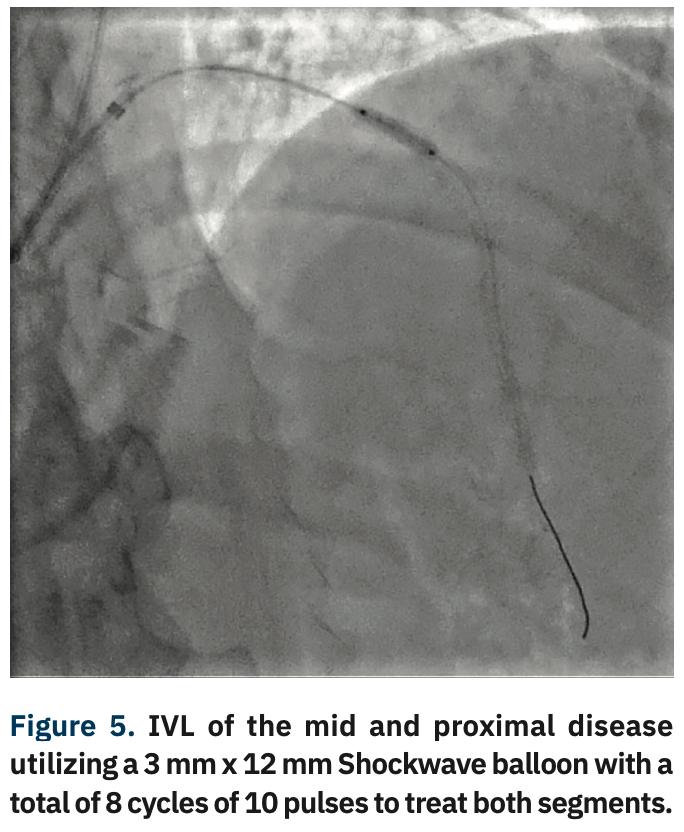

The beauty of intravascular lithotripsy (IVL) is that we now have an on-label calcium modifying tool with demonstrated safety; it is a therapy we can use without adding significant risk to the case. In addition, we are a default radial access lab, with about an 80% to 90% same-day discharge rate. We are big believers in same-day discharge and outpatient PCI, and IVL plays well into that.

Like all centers, we are using more and more advanced imaging, but it is not uncommon for a lesion to be unpredictably difficult to dilate and more heavily calcified than is readily apparent on angiography. In those situations, with a lesion that will not dilate, it is necessary to have a method by which to modify the calcium, even though its presence was not anticipated. This is a particularly precarious situation for operators in non-backup settings. In the past, we would use oversized, non-compliant balloons and take them to very high pressures trying to achieve an adequate final stent result. In exceptionally rare cases, a handful of times over my 10 years here, we would even abort the case mid angioplasty and have to transfer the patient in a less than entirely stable fashion to the high-risk center. Calcium was our Achilles’ heel. We could always filter out the obviously high-risk cases, but there will always be a very small fraction of cases that do not have readily apparent calcium and are non-dilatable. IVL, from a safety standpoint, has been a game-changer for us not only in these cases, but also for cases with readily apparent calcium that otherwise would have required atherectomy. With the use of IVL, we are now at a point where the only cases that we have to either transfer or stage are non-crossable lesions: cases where you can get a wire but not a balloon across, and these are fairly rare.

All of our interventionalists are also active peripheral operators and already had experience with IVL use in the periphery. We found it to be an easy transition when coronary IVL was approved. We moved forward with trialing five coronary cases, which all went well. We have now been doing IVL in the coronaries for several months, with exceptionally good results. We were one of the first in south Georgia to bring IVL to clinical use in the coronaries. We are fortunate to have an administration that is focused on quality and safety. We were initially using IVL before there was a full pass-through for hospital reimbursement, and because of similar cost issues, we were generally using it very selectively in the periphery for extreme cases. We are very pleased with the Centers for Medicare and Medicaid (CMS) decision to improve hospital reimbursement for peripheral cases next year in addition to the recent pass-through language for coronary IVL use.

The beauty of IVL use is that it is essentially an angioplasty, and does not require any more technical skill than a simple PCI. For operators that had previously transferred out patients to high-risk operators, their patients can not only stay local, but they also don’t need to have a transfer of care. Patients keep the continuity of the same provider and the convenience of staying in their home facility. Our group is in somewhat of a unique situation in that we have a backup site partner that has been gracious enough to give us privileges and the hospital is close enough that we can actually do high-risk cases, even though it is not very efficient. I would suspect that the majority, or at least many, of non-backup hospitals instead simply transfer their patients to high-risk operators at tertiary or university centers. IVL is a huge coup for operators that don’t do high-risk cases, because with IVL, they can now treat calcium without experience using high-risk techniques or a volume of cases that supports an advanced technology like atherectomy. IVL is not something that requires a significant learning curve like atherectomy. Even if you do a hundred or 75 cases a year, you are not going to have significant problems doing IVL.

With the ability to more aggressively treat calcium here at our primary site with IVL, there has been a big uptick in our utilization of intervascular imaging such as intravascular ultrasound (IVUS). We are bringing in optical coherence tomography (OCT), with the idea that we will image a much higher fraction of our cases, because of this concept of unappreciated calcification. When we see either moderate or worse calcium, or have a recalcitrant lesion or lesion that is not dilating normally, we are quick to pull the IVUS imaging catheter out in order to assess the arc, length, and width of the calcium. Post IVL, we will generally reassess the lesion to confirm fracture of the calcium. We don’t require IVUS post IVL for stenting, but it definitely is something that makes us feel good about moving forward with stent implantation. More and more, intravascular imaging is going to be a marketable quality indicator. If you are only doing a small percentage of intravascular imaging, I think you are going to be perceived as a lesser quality program. There has been a longstanding resistance to adopting a higher utilization of intravascular imaging, because of the combination of cost and time. I wish that CMS would see the benefit and create a situation where there are not negative financial incentives to doing imaging.